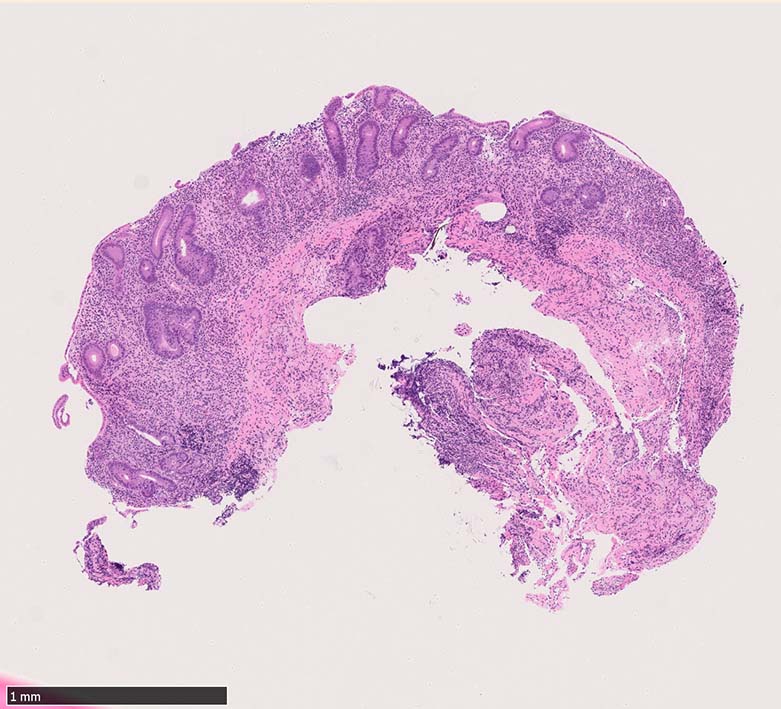

Case presentation

びらんを示す結腸粘膜. 陰窩はdeletion, 萎縮, distortionを呈する. 粘膜固有層には密な慢性炎症がみられ, 好酸球浸潤も多い.粘膜筋板へも炎症細胞浸潤が及ぶ.